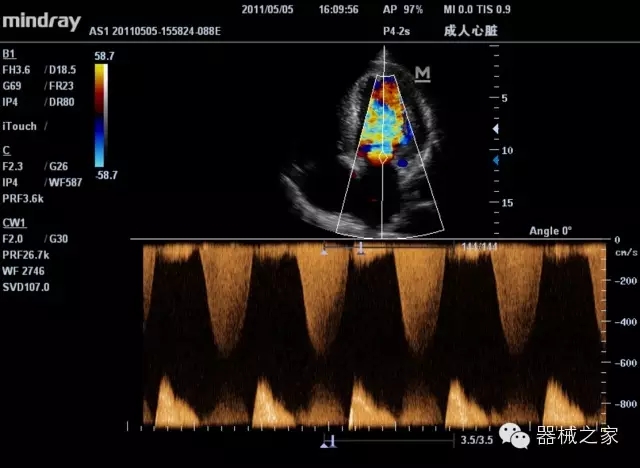

臨床圖片賞析

產(chǎn)品特點(diǎn)

·裝載有采用Multi-Core多核處理的非嵌入式平臺,成像效率大大提高,并且能夠給用戶帶來高速、多任務(wù)并行信號處理體驗(yàn);

·優(yōu)秀的圖像效果、強(qiáng)大的功能體驗(yàn)、豐富的探頭選擇、合理的便攜式設(shè)計(jì),全中文顯示及病人管理界面,使得M7在任何場合、任何時(shí)候都能快速響應(yīng)更好的心血管、腹部、婦產(chǎn)、小器官等常規(guī)超聲檢查以及肌骨、神經(jīng)、顱腦、術(shù)中等新興領(lǐng)域的使用需求;

8倍波束并行處理系統(tǒng)

·在便攜式緊湊平臺上采用更多倍波束并行接收信號處理模式,無論二維還是彩色血流圖像狀態(tài)下,擁有更靈敏的回波頻移捕獲能力,大大提高時(shí)間分辨率,尤其使得心血管表現(xiàn)更為突出;

PSHI?寬帶頻移諧波技術(shù)

·在普通組織諧波的基礎(chǔ)上,通過精確控制的波束形成器,發(fā)射兩組具有相位偏差反向的信號,并采用并行信號處理,數(shù)字化合成并采樣回波信號,在高靈敏度的濾波器的處理過程中獲取更純凈的諧波信號,使圖像具有更加出眾的細(xì)節(jié)分辨率;

iClear®+iBeam?

·智能化按線復(fù)合多角度獲取聲束的原始信號,配合智能化的斑點(diǎn)噪聲識別及控制處理技術(shù),整體提高組織結(jié)構(gòu)細(xì)節(jié)分辨率,任何時(shí)候都能快速響應(yīng),更好的滿足心血管的使用需求;

支持全新3T工藝探頭群

·包括探頭材料、結(jié)構(gòu)設(shè)計(jì)、加工工藝三方面的革新技術(shù)給圖像帶來品質(zhì)的飛躍;